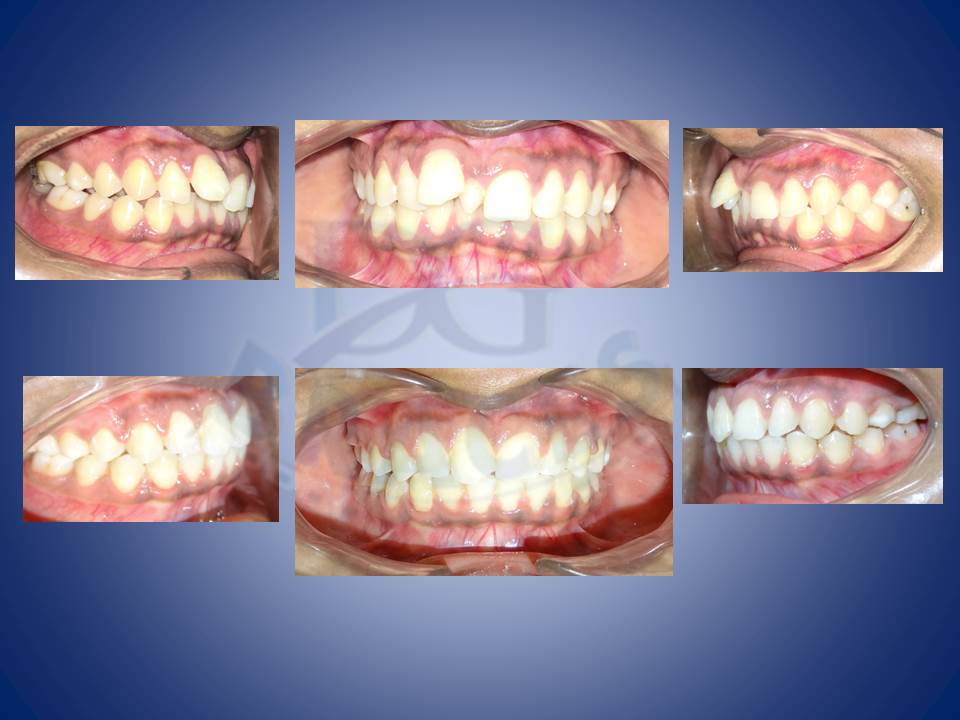

3.Molar distalisation though difficult can be very well done in cases where excessive spaces are required and no extractions can be afforded. Here a palatal Miniscrews was used and distalisation was done with coil springs.